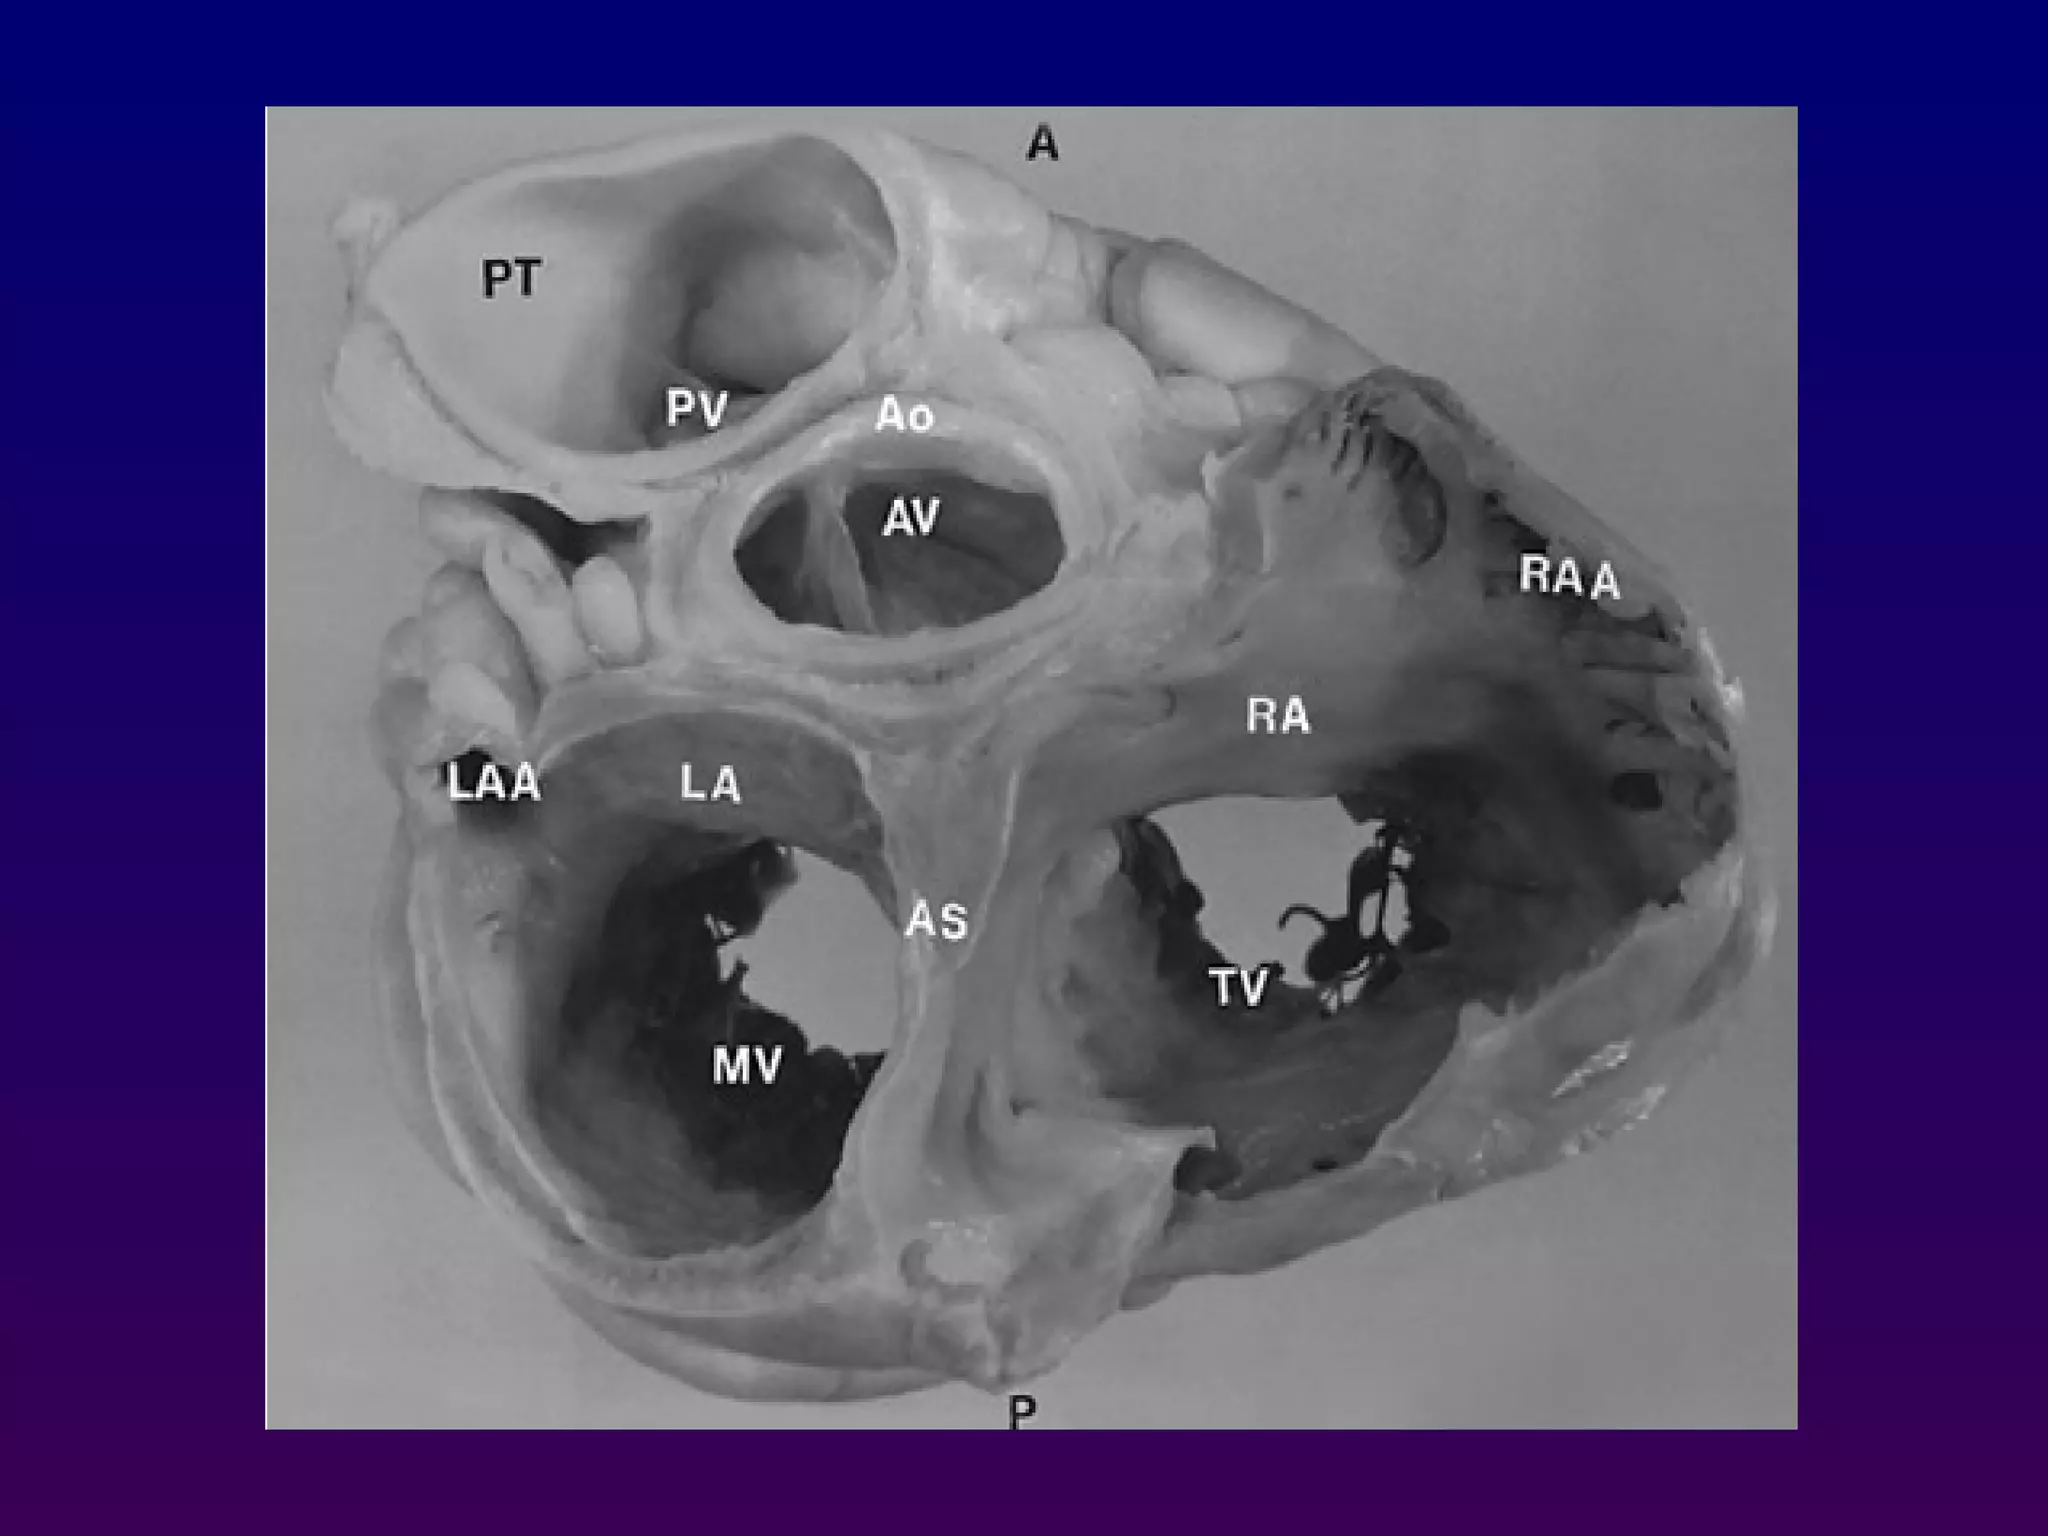

At the basal (aortic valve) level, the right atrium, septal

and anterior leaflets of the tricuspid valve, right

ventricular free wall, right ventricular outflow tract,

pulmonic valve, main pulmonary artery, and left

atrium can be seen "surrounding" the centrally

oriented aortic valve.

All three leaflets of the aortic valve may be identified,

forming a "Y" configuration during ventricular

diastole and "upside-down triangle" during

ventricular systole

At the basal(aortic valve) level, the right atrium, septal and anterior leaflets of the tricuspid valve, right ventricular free wall, right ventricular outflow tract, pulmonic valve, main pulmonary artery, and left atrium can be seen "surrounding" the centrally oriented aortic valve. All three leaflets of the aortic valve may be identified, forming a "Y" configuration during ventricular diastole and "upside-down triangle" during ventricular systole